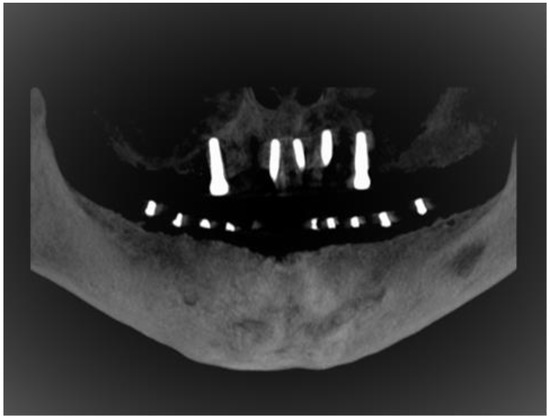

2.4. Study Protocol and Image Analysis

- I.

- Buccalcortical plate to IAN dimension (BCPN): Linear distance from the IAN to the nearest corresponding buccal outer cortical plate.

- II.

- Lingual cortical plate to IAN dimension (LCPN): Linear distance from the IAN to the nearest corresponding lingual outer cortical plate.

- III.

- Alveolar crest to IAN dimension (ACN): Linear distance from the IAN coronally to the midpoint of alveolar crest bone corresponding to the long axis of tooth.